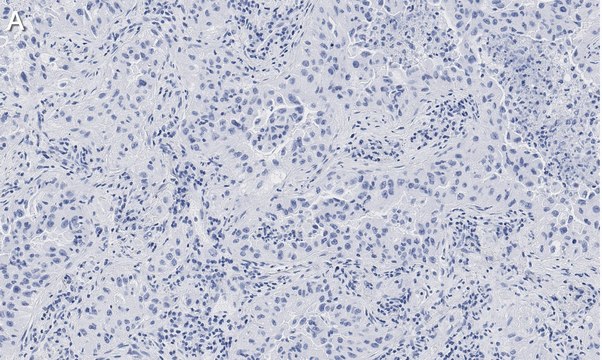

Immunohistochemistry (Paraffin) Analysis: A 1:1,000 dilution from a representative lot detected Integrin pan-alphaV in human lung cancer and human prostate cancer tissue sections.